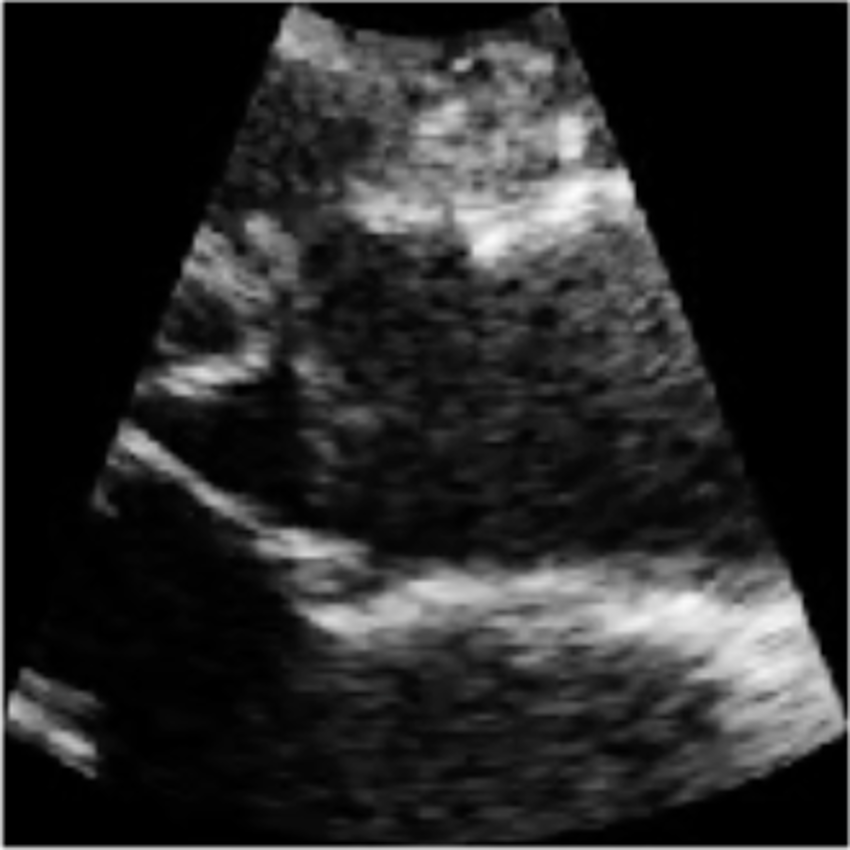

We demonstrate the efficacy of U-LanD on a challenging dataset with sparsely annotated data, namely echocardiography (echo, heart ultrasound). Echo videos, aka echo cine series, have a notoriously noisy nature (sample frames can be seen in Fig. 1), which increases the complication for automated analysis. We tackle the task of left ventricular outflow tract (LVOT) landmark detection [23], as a problem that suffers from an extreme limit of label sparsity; in LVOT training videos, only one frame throughout the entire span of frames has the ground-truth landmark label. In each training video, the expert clinician has annotated locations of two points (coordinates of points used to measure the LVOT diameter), only for one frame (a frame around the mid-systole phase of the heart), where the targeted object, i.e., the aorta, has the highest visibility. For our experiments, we gather a large-scale echo dataset of 4,493 patients, demonstrating that U-LanD can significantly improve the results of state-of-the-art non-Bayesian counterparts. Also, while U-LanD is fully automatic, it can surpass the results of semi-automatic key frame landmark detection involving expert supervision.

For echo LVOT landmark detection in clinical settings, the expert cardiologist examines the echo video, selects a key frame around mid-systole phase of the heart, where the LVOT landmarks are clearly visible, and annotates two points used to measure LVOT length. Sample echo frames and the corresponding visual results and uncertainty maps are presented in Fig. 3. In U-LanD, the BU-Net takes all the frames of the video and predicts landmarks for the recognized key frames, i.e., the frames where the prediction confidence passes the quality criteria explained in Section 4.7, and otherwise discards low confidence predictions regarding them as non-key frames.